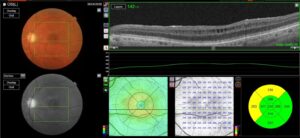

Gravitational tracks in chronic central serous chorioretinopathy: a multimodal imaging case

Patient history A 34-year-old male patient with a history of chronic central serous chorioretinopathy (CSC) [...]